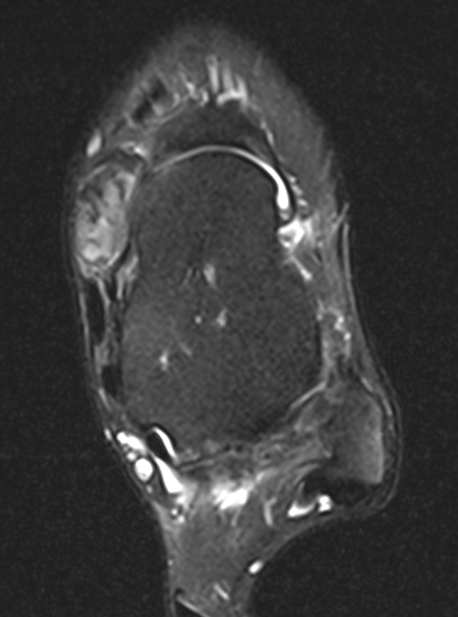

GCT flexor tendon sheath

GCT of tibialis posterior tendon sheath